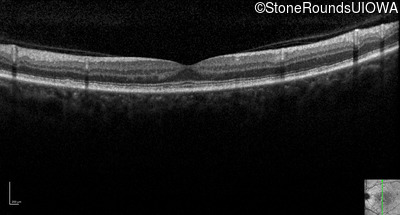

Optical Coherence Tomography - Left - 20/20

Exemplar / OCT Stack

OCT Stack